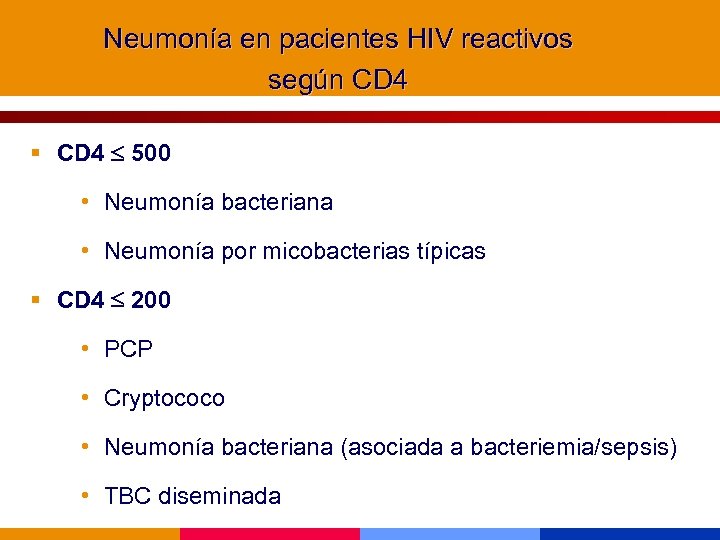

Neumonía en pacientes HIV reactivos según CD 4 § CD 4 500 • Neumonía bacteriana • Neumonía por micobacterias típicas § CD 4 200 • PCP • Cryptococo • Neumonía bacteriana (asociada a bacteriemia/sepsis) • TBC diseminada

Neumonía en pacientes HIV reactivos según CD 4 § CD 4 500 • Neumonía bacteriana • Neumonía por micobacterias típicas § CD 4 200 • PCP • Cryptococo • Neumonía bacteriana (asociada a bacteriemia/sepsis) • TBC diseminada

Neumonía en pacientes HIV reactivos según CD 4 § CD 4 100 § CD 4 50 • Kaposi pulmonar • Histoplasmosis • Neumonía bacteriana (bacilos gramnegativos, estafilococo) • Coccidioidomicosis • Toxoplasmosis • Aspergillus, Candida • CMV • MAC diseminado

Neumonía en pacientes HIV reactivos según CD 4 § CD 4 100 § CD 4 50 • Kaposi pulmonar • Histoplasmosis • Neumonía bacteriana (bacilos gramnegativos, estafilococo) • Coccidioidomicosis • Toxoplasmosis • Aspergillus, Candida • CMV • MAC diseminado